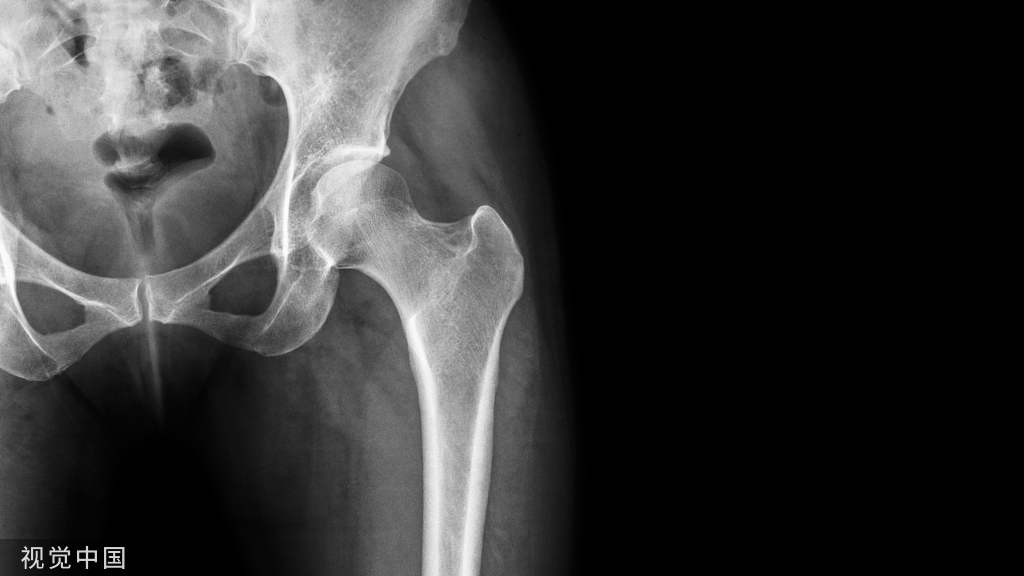

(A)内收和内旋对右髋关节偏移量的影响。与左侧臀部相比,这会产生一种减少偏移量的感觉。(B)骨盆倾斜对肢体长度和偏移量的影响,通过减小髋关节抬高时的偏移量和肢体长度,而对向下旋转的髋关节产生相反的影响。